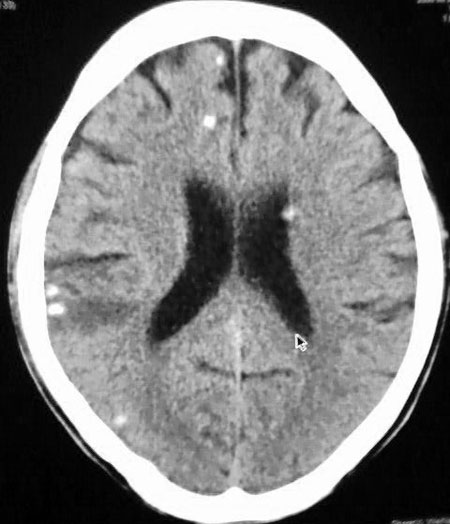

以下是引用守望可可西里在2006-9-6 8:01:00的发言:[br][br] “国内文献进行了脑囊虫病的ct分期:①活动期: ct标志为头节、囊壁、囊液同时存在,分为脑实质小囊型与脑室型;②退变死亡期:ct标志为头节消失、囊腔肿大、虫体崩解,分为单发或多发小囊型、大囊型、葡萄状囊丛型、脑炎型、脑内小脓肿型、脑梗塞型、脑膜炎性③钙化期:标志为囊虫灶转为高密度的钙化结节;④混合期:为活动期、退变期、钙化期病灶混合存在。”[br] 本病例左颞叶、右颞顶叶低密度影,无占位表现,病灶极似脑梗塞。但双侧病灶中偏边缘部位还是有圆形钙化灶,可以考虑为虫体钙化。再加上脑实质内见散在的不对称圆形钙化,其形态类似“大米粒状”,本例应该考虑是脑囊虫病,分期为混合期。